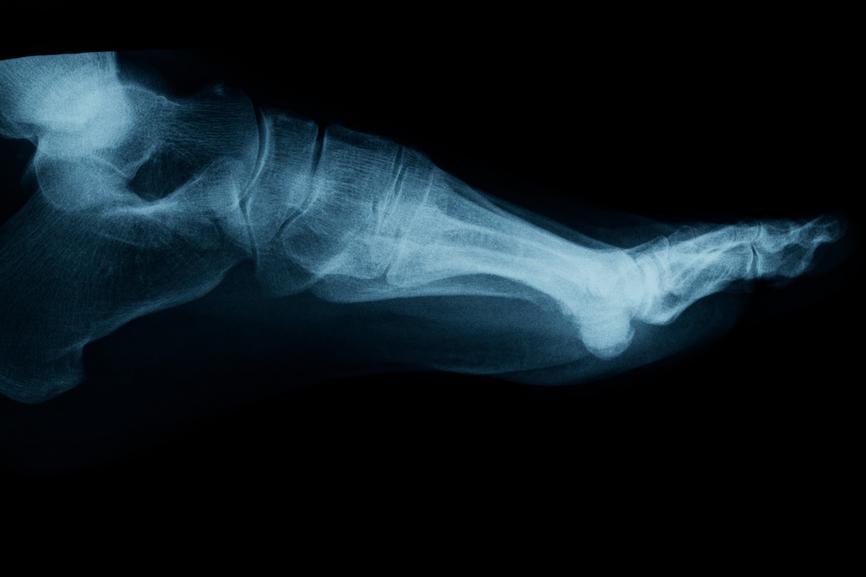

Gout is an inflammatory condition that causes your joints to swell and become painful. A type of arthritis, gout is most common in men. In the vast majority of cases, gout begins in the joint at the base of your big toe, but it can also originate in other toe or even finger joints.

The first noticeable symptoms of gout may include pain or stiffness in the affected joint. As this condition progresses, it causes the affected joint to swell to multiple times its usual size, and gout can spread from one joint to another.

The risk factors for gout are still debated, but the pathophysiology of gout, or the process by which this condition happens in the body, is well understood. Gout begins with a buildup of uric acid (monosodium urate) crystals in the affected joint. These crystals then cause an inflammatory reaction in the joint, leading to pain and swelling.